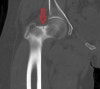

CT : 고관절 피로골절(Stress fracture of the hip)

X-ray 검사를 하기는 하지만 확진은 하기 어렵습니다.

전형적인 소견은 저음영선(radiolucent line), 경화(sclerosis), 또는 골막부위의 새로운 뼈 형성(bone formation)이며 이들은 증상 발생 후 2~4주는 되어야 나타납니다.